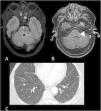

To describe the magnetic resonance imaging (MRI) findings for the most common inflammatory and immune-mediated diseases that involve the brainstem.

ConclusionInflammatory lesions involving the brainstem are associated with a wide range of autoimmune, infectious, and paraneoplastic syndromes, making the differential diagnosis complex. Being familiar with these entities, their clinical characteristics, and their manifestations on MRI, especially the number of lesions, their shape and extension, and their appearance in different sequences, is useful for orienting the radiological diagnosis.